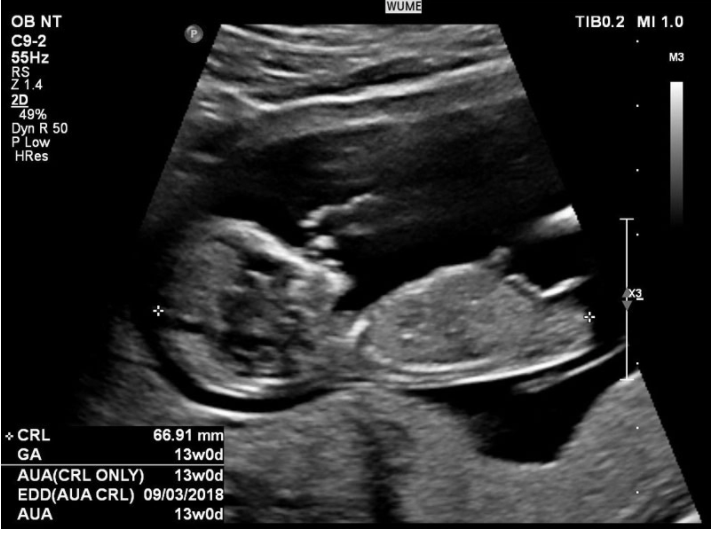

胎儿生长指数有很多术语。下面介绍几个胎儿重要指标的名词和缩写,供孕妇参考:

- GA:从末次月经第一天算起的胎龄。

- CRL:头对接长度。

- BPD:双顶径,即水平跨过颞骨测量的最大直径。

- FL:股骨的长度。

- EFW:估计胎儿的体重。

- EDD:预计出生日期。

第二次妊娠检查和超声检查(11 周 - 13 周 6 天)

- 颈项透明层的超声测量。